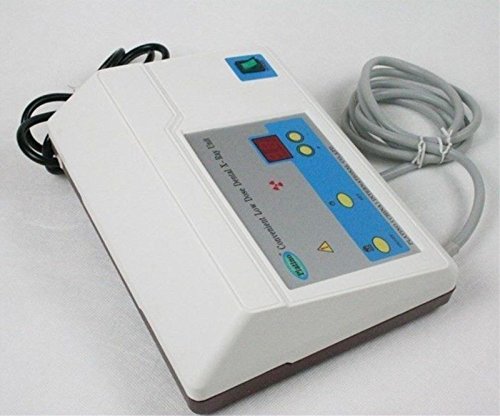

Features: The tube voltage frequency of this machine is 30 KHz, and the tube current is 0.2 MA. The radiation scope is at an angle of 24 degrees, located within a distance of 1.2 meters ahead. Toshiba 0.3mm x 0.3mm micro-focus tube No protective operation room is needed when installing the complete machine Compact in volume, light in weight, convenient for carrying Time is adjustable, high contrast of picture, imaging in focus There are vacuum components and high-pressure parts inside of the machine, so for your safety and the maintenance of the machine Non-film inspection and storage can be realized when corresponding to a sensor Specifications: Voltage: 110v±10% and 220V±10% Power: 24V 8000MA Charger: 220V/110V, 50Hz Tube current: 0.1mA Rating: 60W Frequency: 30 KHz Exposure time: 1-9 seconds optional Leak radiation: Focus Skin Distance: >20cm Tube voltage: 60KV Relative Humidity(RH) Storage conditions: 5-40 degrees Celsius, relative Humidity Net weight: 5.5 kg Dimension: 47 x 42 x 19 cm Content: Main Unit x 1 Dental Film Position x 1 Charger x 1 Dental Films for Test x 5 English Manual x 1 Warranty Card x 1